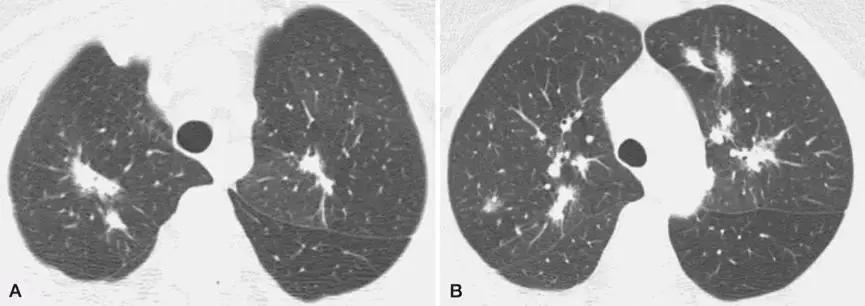

2、影像学是诊断线索

OP的影像表现:实变(周围、沿支气管血管束):80~95%;磨玻璃影:60~90%;小叶间隔增厚:55%;「反晕征」:20%;结节或团块:15~50%;还有「游走性」的特点。

反晕征:

结节或团块(需要和肿瘤鉴别):